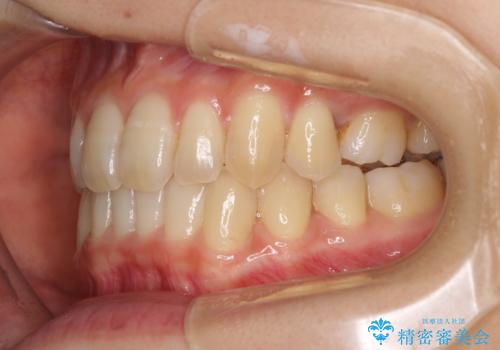

奥歯の反対咬合 上顎骨を拡大してインビザラインで矯正

- 奥歯の反対咬合を気にして来院された患者様です。

反対咬合は上顎骨の幅が下顎骨よりも小さいことが原因なので、拡大装置により骨幅を広げて上下関係を改善し、その後インビザラインにて歯並びを整えることとしました。

反対咬合が改善され、食いしばり癖もなくなり、顎関節の負担が軽減されました。